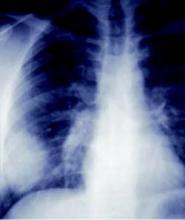

When to order chest x-ray?

Clinical decision rules detected 59% of pneumonias, vs just 33% with physician judgment.